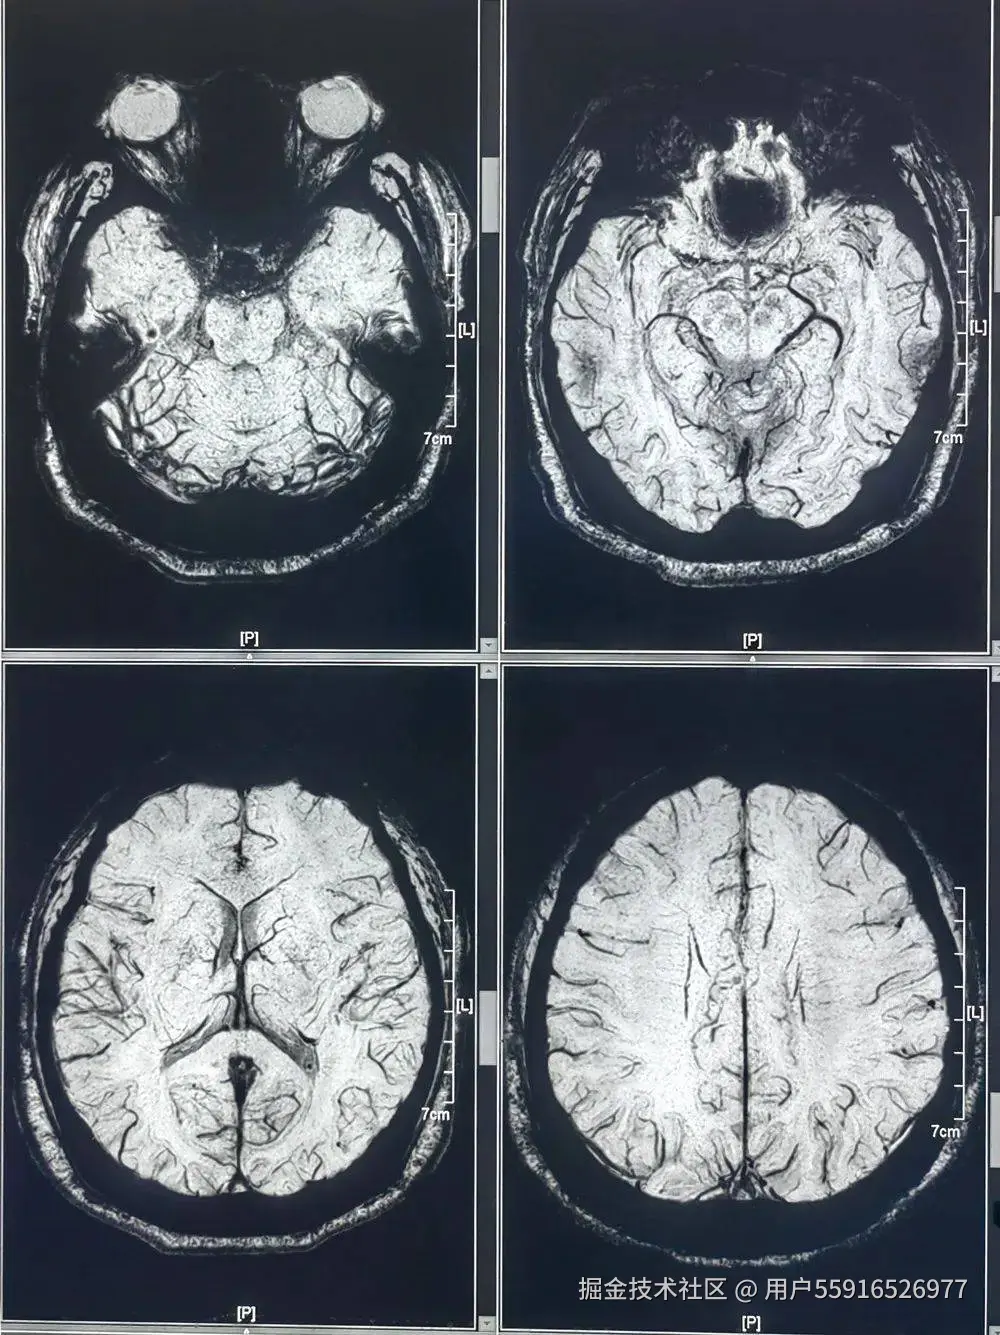

北京精诚博爱医院影像科简介:

北京精诚博爱医院影像科集常规X线、CT、MRI等影像诊断手段,科室拥有数字化摄影机(DDR)、数字床旁摄影机、飞利浦计算机体层摄影机(128排CT)、飞利浦3.0T核磁共振成像机(MRI)等先进检查设备。对患者全身各系统、各部位进行影像学检查,对患者疾病早期发现、早期诊断与早期治疗具有重要意义。科室已经实现全面数字化成像,诊断准确,网络传输,远程会诊,大大缩短候诊时间,优质高效。

影像科现有工作人员近20人,梯队建设合理,学术带头人均有三甲医院工作数十年经验。科室团队均具备丰富的专业知识和临床经验,操作技术娴熟,工作严谨,为每一位患者提供专业、细致的医疗检查服务。